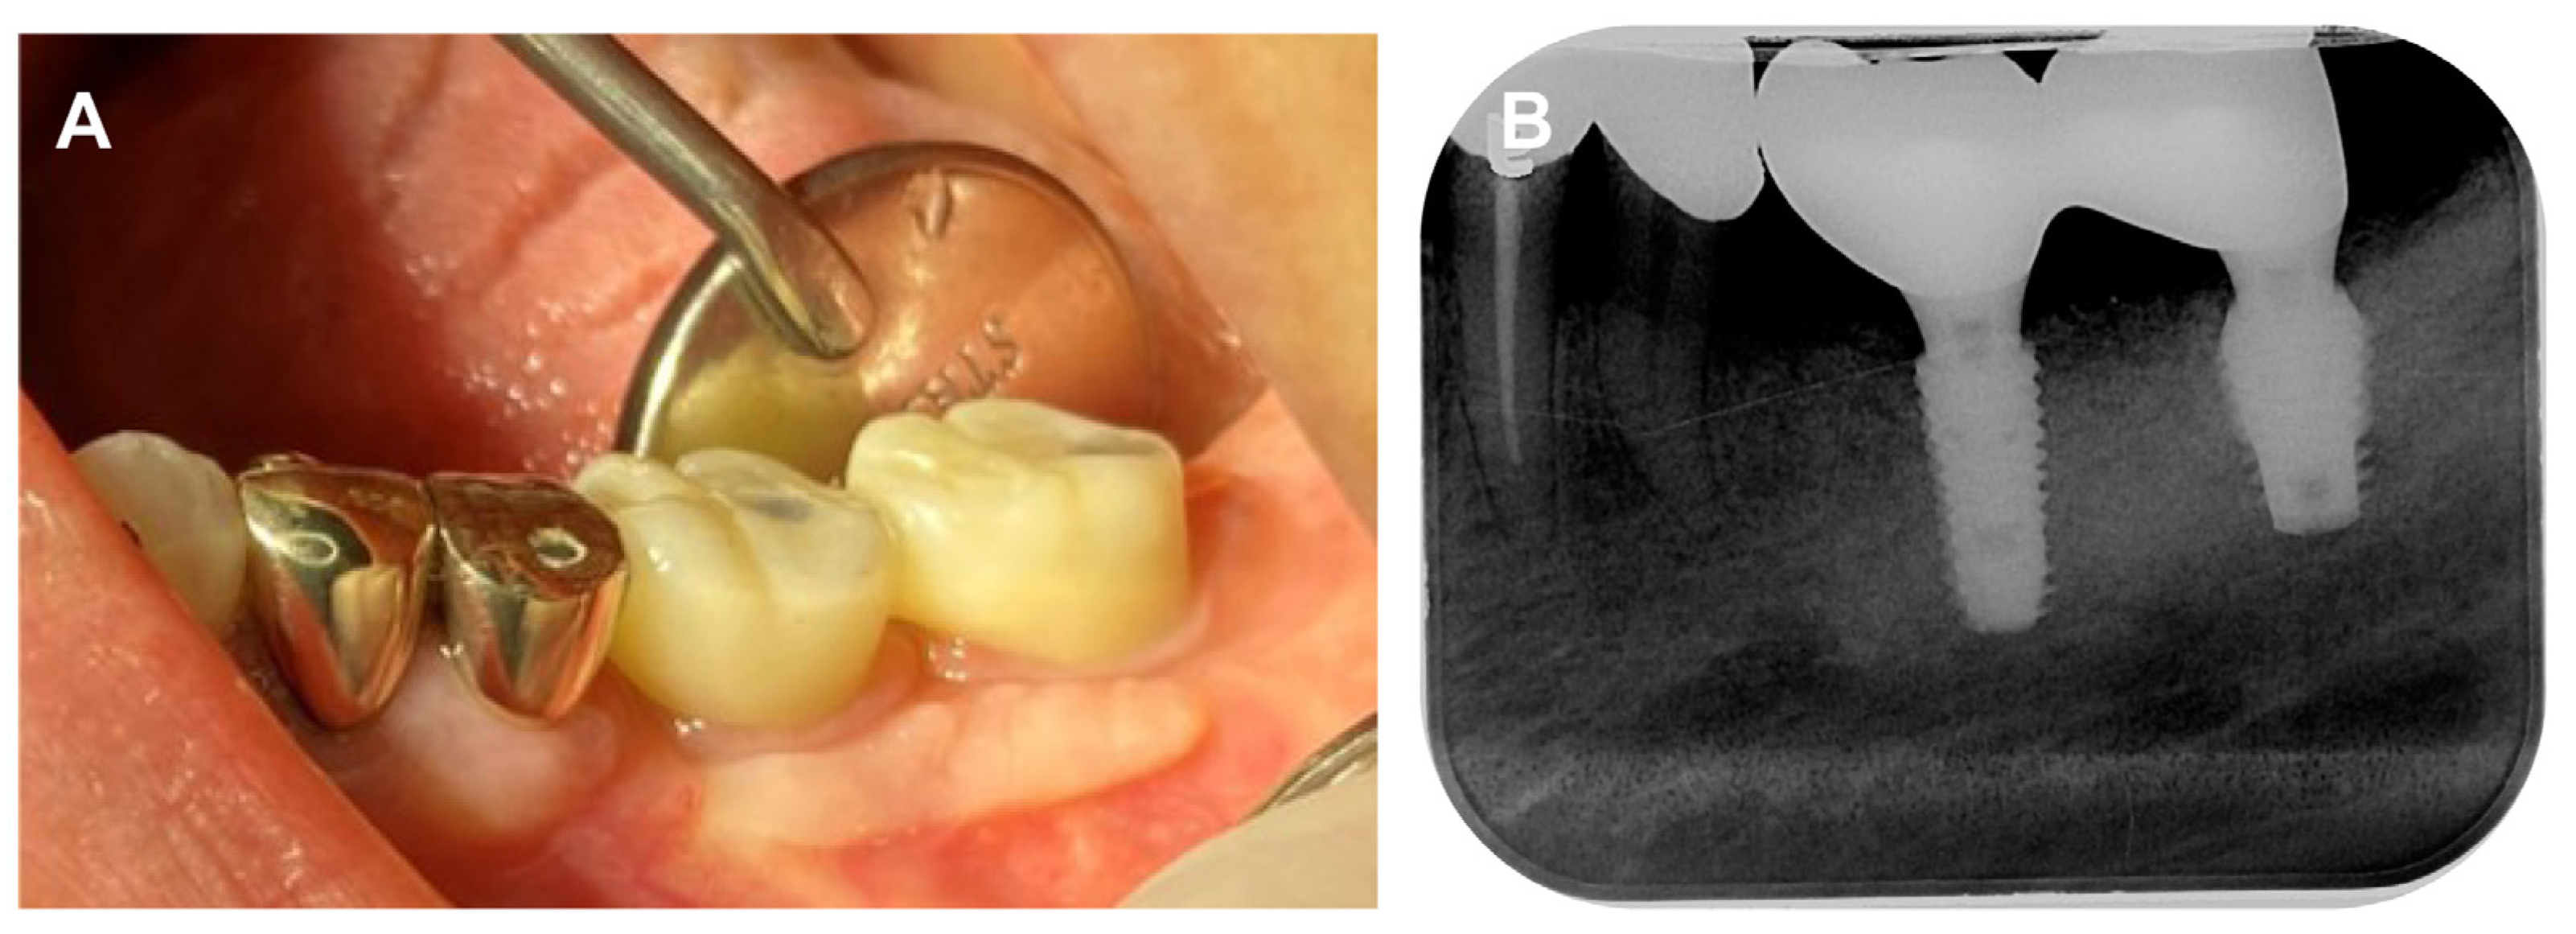

A 78-year-old female patient visited the dental clinic of Daegu Catholic University Medical Center, complaining about a loss of the mandibular left first molar (Figure 1A). The patient had a medical history of hypertension, but she was not taking any medications which needed to be discontinued during the implant procedure. The patient was a non-smoker. For the treatment of choice, it was decided to restore a single implant prosthetic restoration. As a surgical method, flap surgery was planned for bone grafting and implant placement. After the intraoral and radiological examination of the patient, scaling was performed prior to implant placement. The patient received the same pharmacologic protocol of prophylactic oral antibiotics. Amoxicillin sodium (Augmentin; Ilsung pharmaceutical, Seoul, Republic of Korea) with a dosage of 500 mg was to be taken 3 times a day and prescribed routinely, from 1 day before the procedure to 7 days after the procedure. Then, a 4.5 × 10.0 mm implant (AR fixture; Biotem, Seongnam, Republic of Korea) was placed (Figure 1B) with a good initial fixation torque of 40 N/cm2 at placement. After a sufficient healing period of 3 months, the patient received the implant prosthesis.

The multi-abutment (Toplan Co., Seoul, Republic of Korea) was connected to the osseointegrated implant fixture. The height of the multi-abutment was determined using a gingival gauge (Figure 2A), and then the multi-abutment was tightened with a torque of 35 N/cm2 (Figure 2B).

Figure 2. (A) Multi-abutment height determination with gingival gauge, (B) Multi-abutment connection.